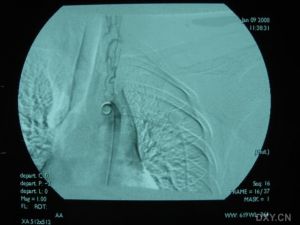

7.動脈造影,超聲都卜勒,ECT等檢查證明,受累的頭臂動脈和下肢動脈顯示狹窄或閉塞,降主動脈、腹主動脈呈縮窄表現。